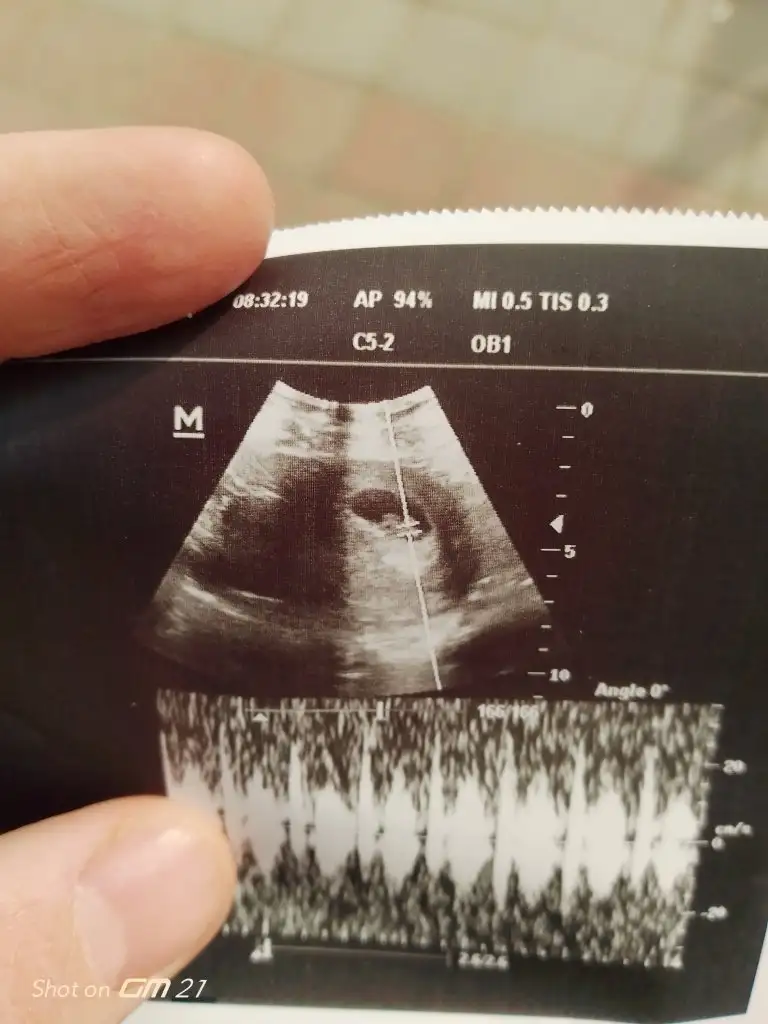

8+6 haftalık ama ultrason da 8+1 ile uyumlu doktor hiç bir şey söylemedi hatta oruç tutabilir miyim dedim dalga geçer gibi sence dedi daha da bişey demedi bizim aileye tek yumurta ikizleri var öle bi durum mevcut mu dedim cevap alamadım ilçede tek doktor ultrasyon görüntüsüne göre bolemi oluyo kalp atışı duyduk